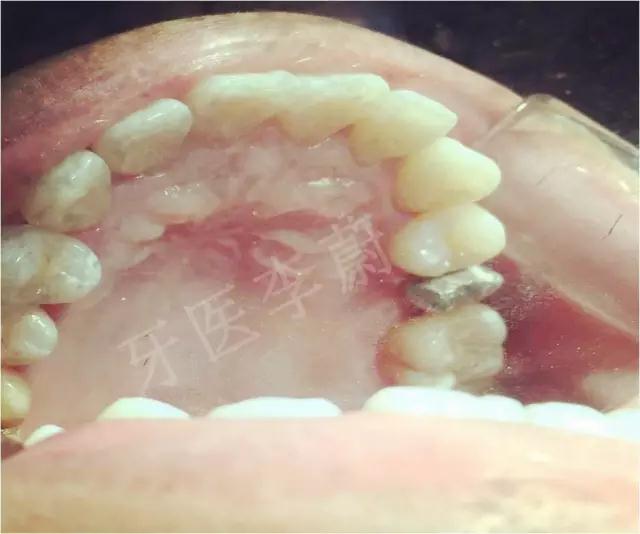

口腔检查:15冠部龋损,探及大量腐质,舌侧冠折至龈下约2mm,近、远中壁亦部分龋坏,松动Ⅰ°,叩痛(-) ,牙龈无瘘管,舌侧及近中被龈组织覆盖。

15牙二氧化锆烤瓷冠舌面观

15牙戴入二氧化锆烤瓷冠